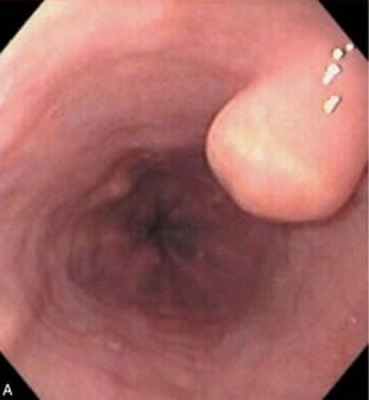

Всем больным с подозрением на опухоль пищевода показана фиброэзо- фагоскопия. При этом при внутрипросветных опухолях выявляют округлые образования, покрытые малоизмененной слизистой оболочкой. Во время их инструментальной пальпации возможна умеренная кровоточивость слизистой оболочки. Прицельная биопсия с последующим морфологическим исследованием материала позволяет установить окончательный диагноз, верифицировать гистологическую структуру опухоли.

Для внутристеночных опухолей характерно наличие образования, выступающего в просвет пищевода. Слизистая оболочка над ним, как правило, не изменена, рельеф ее сохранен или несколько сглажен. При изъязвлении опухоли можно обнаружить дефект слизистой оболочки. Следует подчеркнуть, что при наличии интактной слизистой оболочки над новообразованием биопсию при выполнении эзофагоскопии производить не обязательно вследствие ее неинформативности. Кроме того, это связано еще и с тем, что при оперативном лечении внутристеночных опухолей обычно удается вылущить опухоль без повреждения покрывающей ее слизистой оболочки.